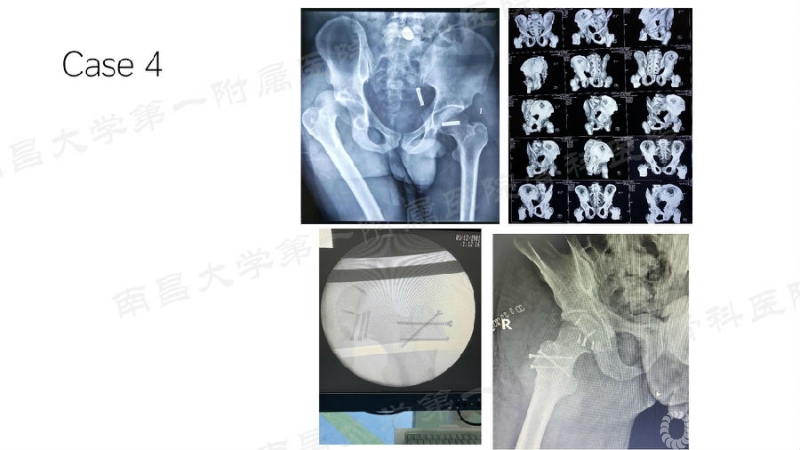

病例四